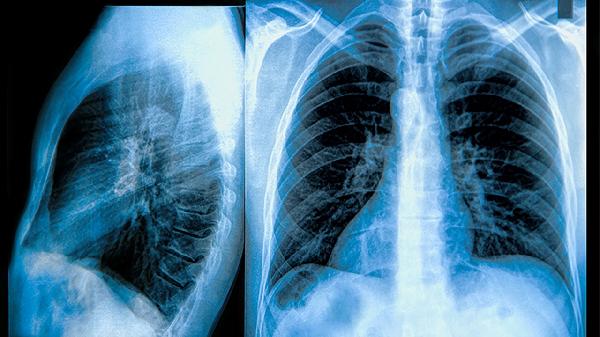

肺门及纵隔多发淋巴结肿大怎么办

肺门及纵隔多发淋巴结肿大可通过抗感染治疗、结核病规范用药、肿瘤综合治疗、免疫调节治疗、定期影像学复查等方式干预。该症状通常由肺部感染、结核分枝杆菌感染、恶性肿瘤转移、自身免疫性疾病、结节病等原因引起。

每3-6个月进行胸部CT随访,观察淋巴结大小变化。稳定的小淋巴结(短径<1cm)可能无需特殊处理。新发肿大或融合成团需警惕恶变,建议进行EBUS-TBNA等微创活检。复查期间出现咳嗽加重、呼吸困难等预警症状应及时就诊。